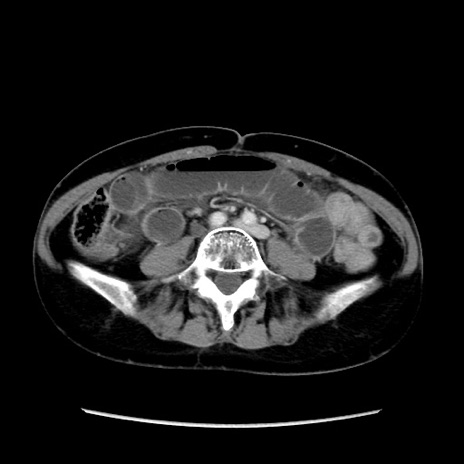

症例32(横断像)

【症例】40歳代 女性

【主訴】上腹部痛、嘔気・嘔吐

【現病歴】約9時間前頃から急に上腹部痛、嘔気、嘔吐が出現。改善しないため救急要請。

【既往歴】子宮頚癌(広汎子宮全摘術、放射線療法)、腸閉塞

【身体所見】腹部:平坦、軟、腸雑音亢進、上腹部を中心に腹部全体に圧痛あり。

【データ】WBC 8400、CRP 0.03